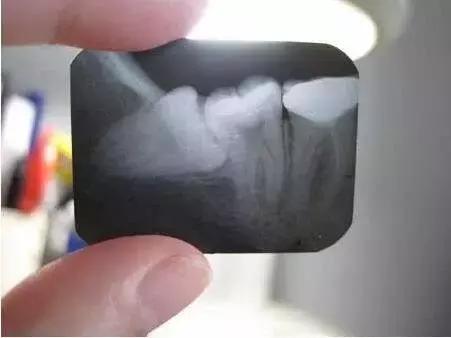

1.由于人类食物的变化而带来咀嚼器官的退化,下颌骨有逐渐缩小的现象,因而造成牙列与颌骨不协调,智齿萌生的位置不足,成为智齿阻生的原因。

3.临床上智齿部分萌出,也是伴发智齿冠周炎的直接原因。智齿在萌生过程中,冠部往往被牙龈瓣覆盖,与牙冠之间形成较深的盲袋,食物及细菌极易嵌塞于盲袋内,一般很难通过漱口和刷牙被清理干净;加之口腔内有非常适宜的温度和湿度,致成为细菌繁殖的温床。

3、 会导致牙齿不齐:当智齿开始萌出,有可能将牙齿向前推压,造成前牙拥挤,若是已有轻度拥挤,排列不齐的前牙,情况将更趋严重。如果发现下颌骨没有足够位置容纳智齿,或曾作过牙齿矫正治疗的患者,若智齿萌出对正畸后的稳定有可能造成影响时,应及早拔除,预防前牙排列不齐。

4、 会影响其他牙齿龋坏:阻生智齿能使第二磨牙龋坏。向前倾斜的智齿,其牙冠顶在前牙的颈部,这两颗牙之间形成一个滞留区,由于食物残渣的滞留,得不到正常清洁,细菌繁殖产酸,腐蚀牙齿,造成第二磨牙牙颈容易发生龋齿,往往就诊时已不能保留,需要拔除。